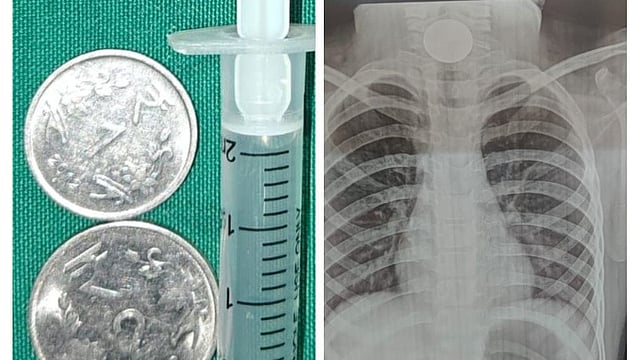

குழந்தையின் தொண்டையில் சிக்கிய நாணயங்கள் மற்றும் எக்ஸ்ரே படம்.

கடந்த செவ்வாய்க்கிழமை மாலையில் 1 ரூபாய் நாணயம், 2 ரூபாய் நாணயம் ஆகிய இரண்டு நாணயங்களை வைத்து சிறுமி விளையாடி கொண்டு இருந்துள்ளார்.

இந்த நிலையில் வாயில் போட்டு கொண்டு அந்த சிறுமி விளையாடிய போது 2 காசுகளும் தொண்டையில் சிக்கியுள்ளது.

அப்போது எக்ஸ்ரே எடுத்துப் பார்த்த மருத்துவர்கள், உணவு குழாயில் சிக்கி இருந்ததை கண்டறிந்தனர்.

குழந்தைக்கு மயக்க ஊசி செலுத்திய மருத்துவர்கள், அறுவைச் சிகிச்சை செய்து 2 காசுகளையும் வெளியே எடுத்தனர். இதனால், குழந்தையின் பெற்றோர் நிம்மதியடைந்தனர். குழந்தையை காப்பாற்றிய மருத்துவர்களுக்கு, குழந்தையின் பெற்றோர் நன்றி தெரிவித்தனர்.